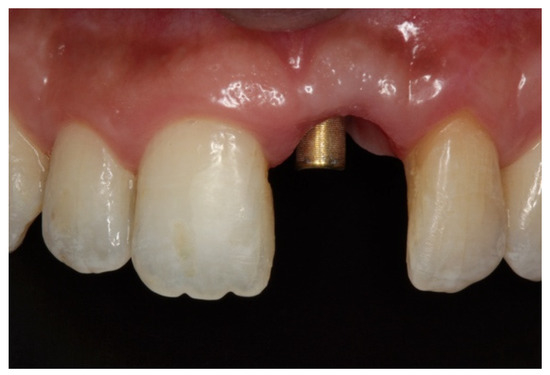

Implants were activated 6 to 10 months after placement. A temporary acrylic crown was screwed to the implant, and a temporary resin abutment (Peek® BioHorizons, Birmingham, AL, USA) was used to shape the cervical contour and emergence profile (Figure 6).

Figure 6.

(A) Initial provisionalization (adhesive bridge). (B) Subsequent customized provisionalization, screwed down to create the emergence profile.

Figure 9.

(A–C) Placement of the porcelain crown.